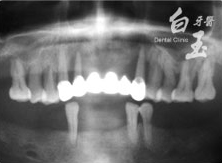

治療後